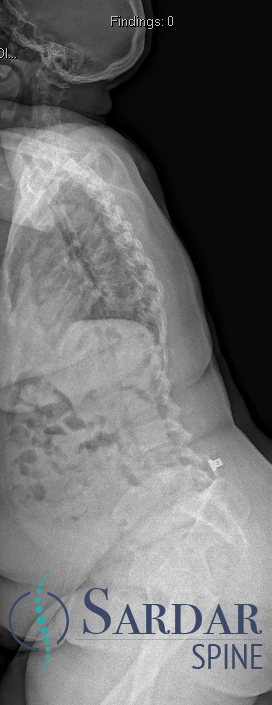

From robotics and AI-driven surgical planning to virtual modeling and custom implants, I’ve embraced a combination of tools that allow me to create tailored surgical plans for my patients—particularly those with scoliosis and spinal deformities.

What sets my approach apart is the seamless integration of these advanced technologies to ensure unparalleled accuracy and better outcomes for each patient.